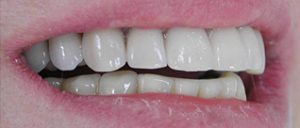

J’ai une ou plusieurs dents qui manquent que je veux remplacer mais sans toucher aux autres.

Solution : on va remplacer ces dents par la mise de un ou plusieurs implants.

Des dents qui manquent.

Les dents sont remplacées par des couronnes individuelles sur implants. Sourire final.